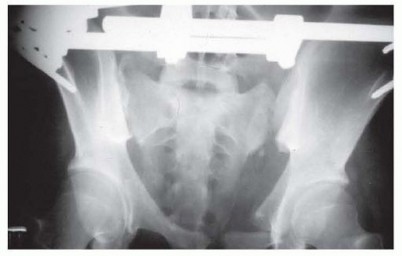

-

FIG 4 • Anterior external fixation of the pelvis does not confer posterior stability. In this example, left posterior sacroiliac diastasis is unresolved. In such cases, anterior external fixation may effectively manage hemodynamic instability but does not offer structural posterior stability. (From Peters P, Bucholz RW. The assessment of pelvic stability following pelvic ring disruptions. Tech Orthop 1990;4:52-59.) 313 The surgeon characterizes, if applicable, the presence and type of pelvic instability, assigning the injury pattern to a classification scheme. The intended purpose of external fixator must be defined (resuscitation or provisional vs. definitive stabilization). If for purposes of provisional stabilization, the surgeon should determine the anticipated timing, sequence, and method of subsequent definitive stabilization. Frame design and pin location are selected (anterior iliac crest, supra-acetabular, posterior C-clamp) based on the pelvic injury pattern, the patient's hemodynamic status, the available imaging, and surgeon familiarity. An immediate presurgical pelvic radiograph is obtained to assess the impact of retained bowel gas or contrast on imaging capability (if required). ## Positioning The patient is placed supine on a radiolucent table. Adequacy of imaging and efficacy of closed reduction maneuvers are confirmed. Preparation is done from the umbilicus to the anterior thighs, including both iliac crests. One or both lower extremities are included circumferentially as required to effect rehearsed closed reduction maneuvers. ## Approach Adequate fixation and accordingly proper pin placement are the principal requirements for restoring pelvic stability when applying an external fixator. Pins for purposes of anterior pelvic external fixation may be placed either in the anterior iliac crest or in the supraacetabular region ( FIG 5). Ease of insertion is an important attribute when applying a resuscitation frame.